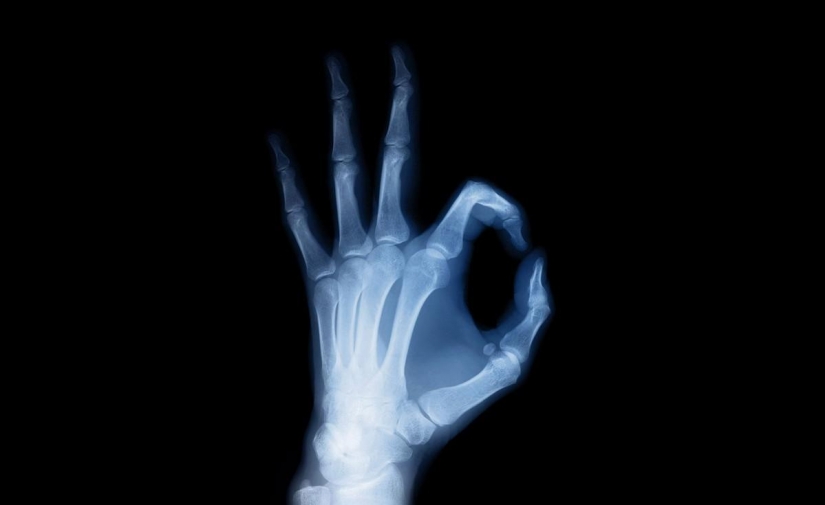

2. Los rayos X